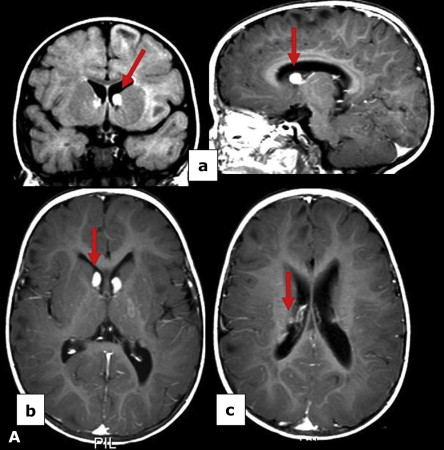

Incontinentia Pigmenti

(色素失調病,Bloch-Sulzberger syndrome )

X顯性

GENE: NEMO (NFκB Essential Modulator)

剛出生

• 先天免疫 gg

• CNS (30%)

• 眼睛 (35%): 斜視(strabismus)、眼球震顫(nystagmus)、白內障(cataracts)、視網膜血管異常、視神經萎縮

• 皮膚: 水皰期 → 疣狀期 → 色素過度沉積階段 → 萎縮和脫色階段

• 口腔: 同 EDA mutation

水皰期

上皮內裂解,內部充滿嗜酸性球

疣狀期

過度角化, acanthosis, papillomatosis

色素過度沉積階段

皮下結締組織 melanin-containing macrophage,即黑色素失調(melanin incontinence) alt text